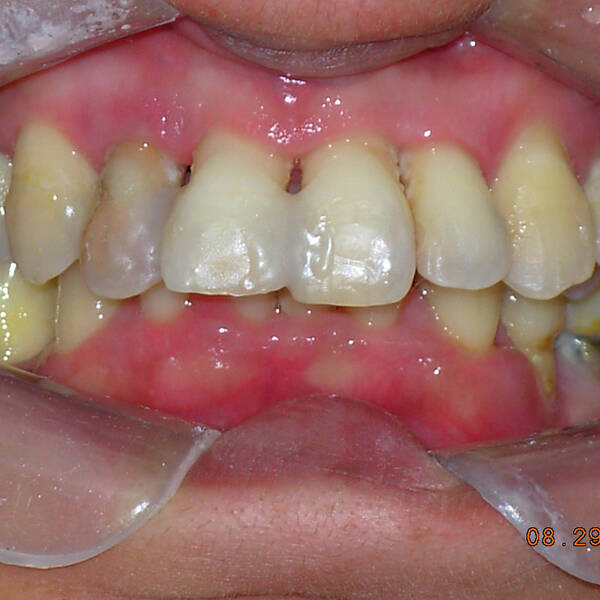

Na Clínica Pontes Odontologia, somos referência em implantes dentários em Fortaleza, oferecendo tratamentos de alta qualidade e tecnologia de ponta. Os implantes dentários são estruturas de titânio posicionadas cirurgicamente no osso maxilar ou mandibular para substituir as raízes dos dentes ausentes. Essa técnica permite a fixação de próteses personalizadas, restaurando a função mastigatória, a estética e a autoestima dos nossos pacientes.